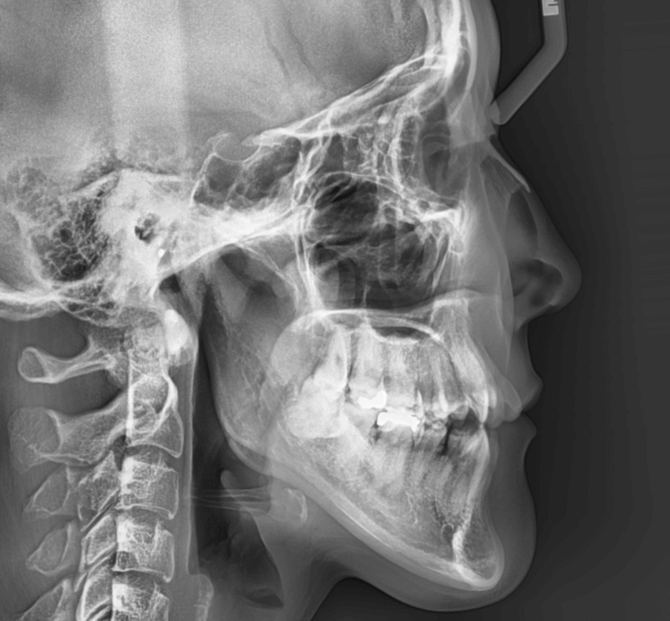

開咬と口元の突出感が気になる

| 年齢・性別 | 22歳の女性 |

|---|---|

| 主訴 | 上下顎前歯部に開咬と口元の突出感を気にされて来院された。咬み合わせや審美的な改善を希望されていました。 |

| 治療期間・回数 | 3年9ヶ月・32回 |

| 費用 | 930,000円 |